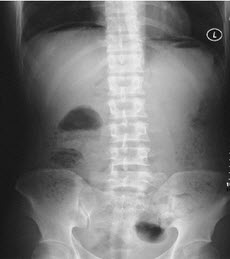

该X片可诊断为()

A、气腹

B、肠梗阻

C、正常腹平片

D、尿路结石

E、液气腹

正确答案:

A